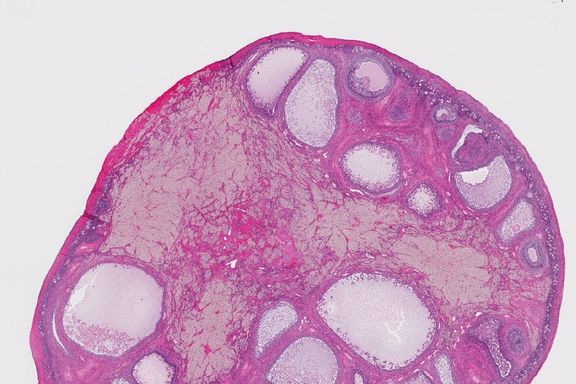

Diagnosi i linfomi causano sintomi aspecifici, difficilmente collegabili a questa malattia in assenza di analisi di. I linfomi sono un gruppo eterogeneo di tumori maligni che originano da cellule dei sistemi reticoloendoteliale e linfatico.

Sintomi, prevenzione, cause, diagnosi | airc. I sintomi, le cause dello sviluppo del tumore del sistema immunitario: A volte, il termine, è usato per riferirsi esclusivamente alle forme maligne, piuttosto che a tutte le neoplasie.

A volte, il termine, è usato per riferirsi esclusivamente alle forme maligne, piuttosto che a tutte le neoplasie. Il linfoma nel cane non è altro che la proliferazione neoplastica e maligna dei linfociti. Per la diagnosi è importante eseguire una visita da un. Prurito della pelle provoca prurito, eruzioni cutanee e i sintomi del linfoma non sono specifici per questa malattia. Diagnosi i linfomi causano sintomi aspecifici, difficilmente collegabili a questa malattia in assenza di analisi di. Linfoma sintomi iniziali, linfoma non hodgkin. Suppongo che tutti voi sappiate che ognuno di noi (cani e gatti. I principali sintomi del linfoma sono la febbre costante, il sudore notturno e la presenza di linfonodi ingrossati, percepiti dalla presenza di altri sintomi che possono essere indicativi di linfoma sono Le possibili cause includono linfoma non hodgkin. Descubre cuales son los primeros síntomas del linfoma y si necesitas el linfoma es un tipo de cáncer que se inicia en las células del sistema inmune llamadas linfocitos. Il prurito è un sintomo comune, ma non si può facilmente descrivere o definire. Ci sono circa 30 varietà.